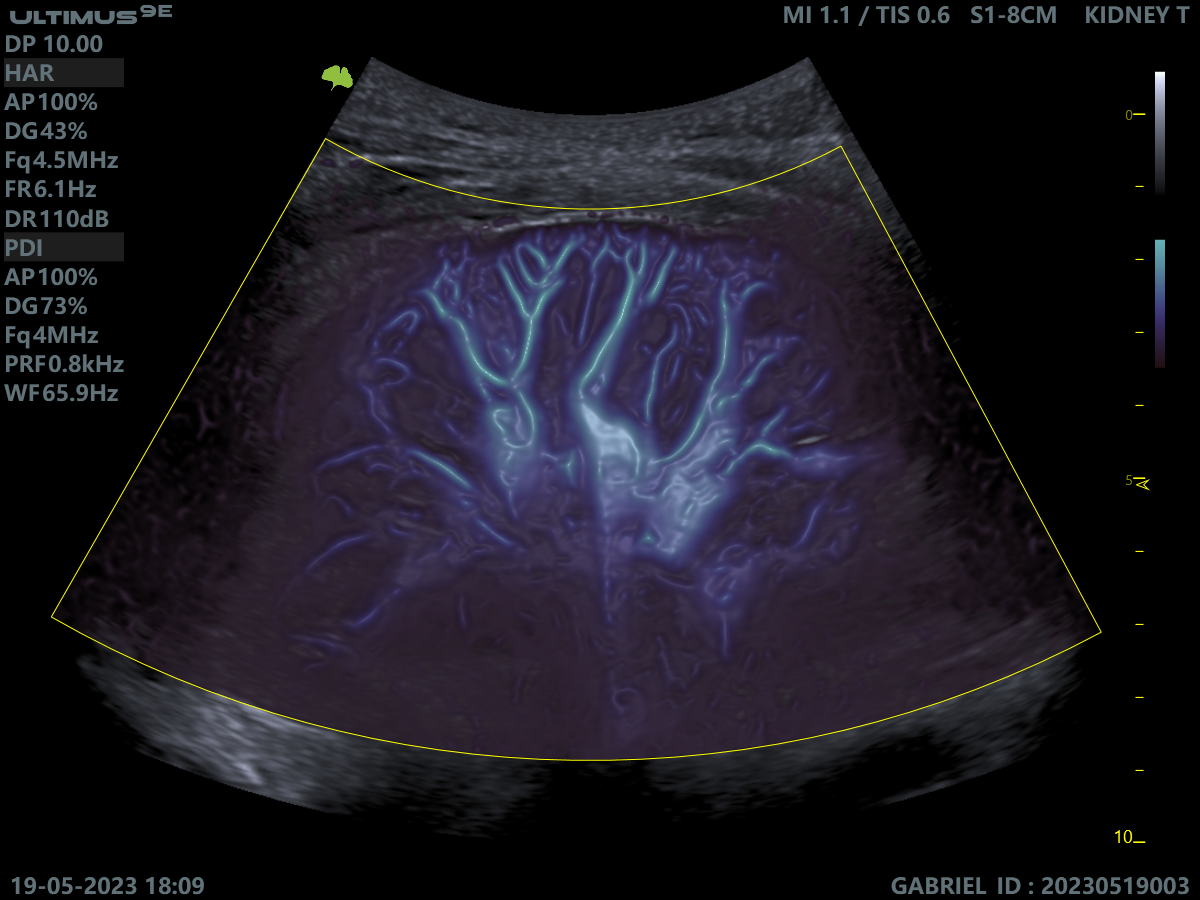

Клінічні зображення, що демонструють якість діагностики та можливості обладнання

Клінічне зображення 4